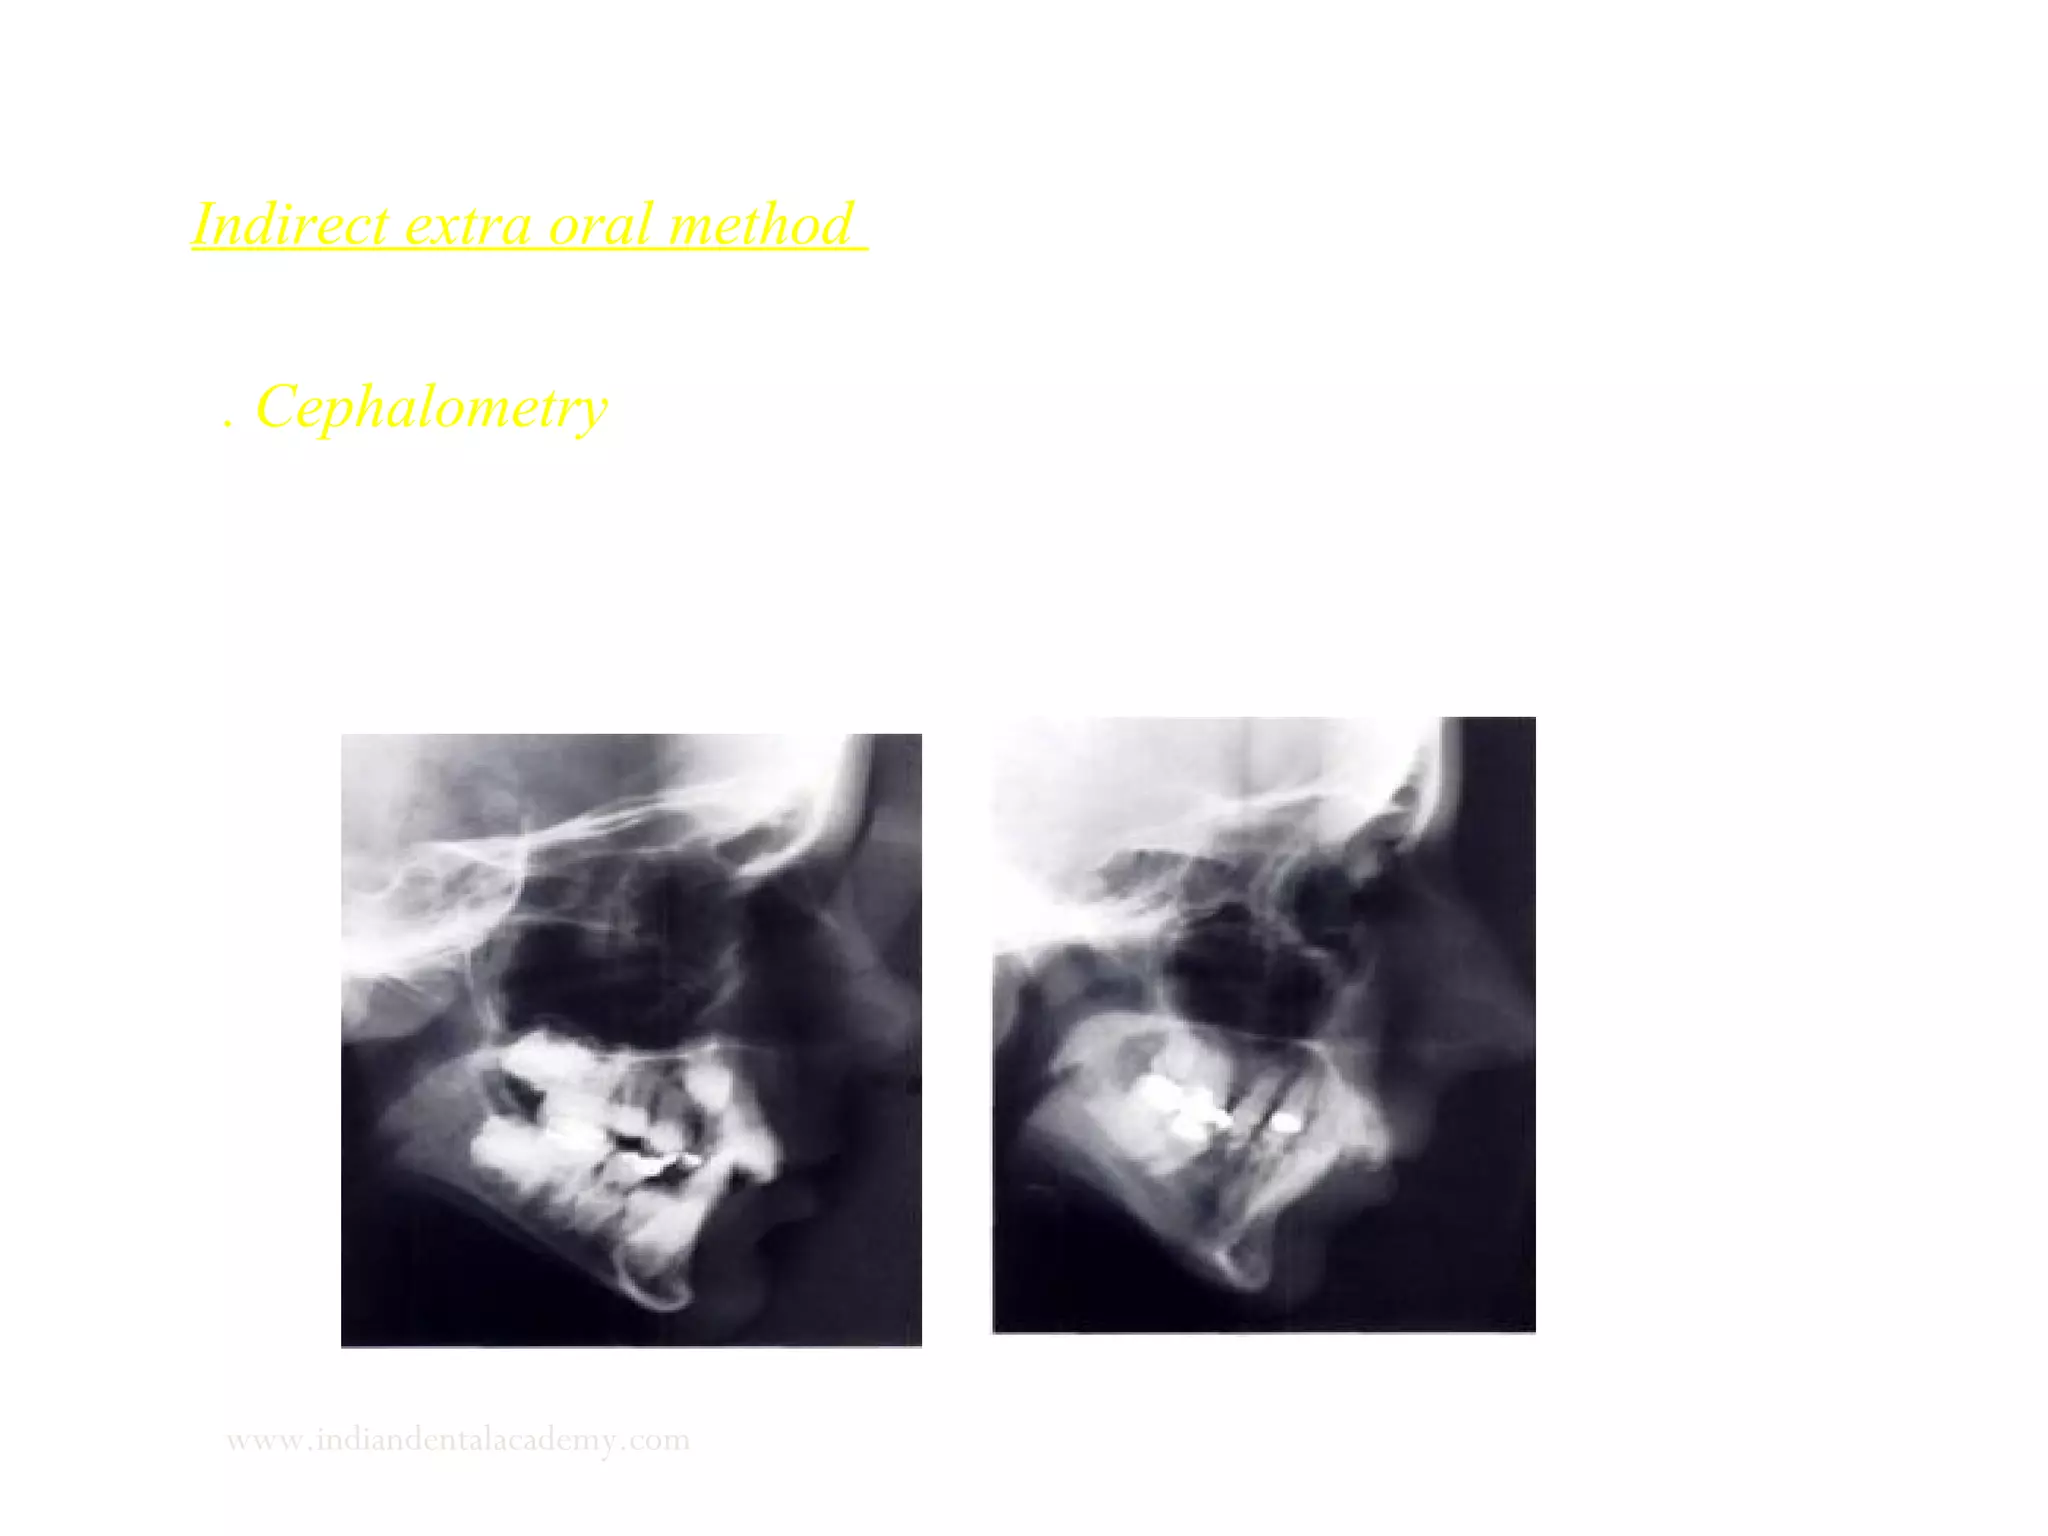

Indirect extra oral method

1. Cephalometry - the clinician takes two or three lateral cephalograms

under identical exposure and patient position conditions

www.indiandentalacademy.com

Examination of tongue posture

Cephalometric analysis Use of radio opaque coating such as barium

paste on the tongue enhances visualization.

Cephalometric analysis of the tongue

Class II DIV I (Left) Class III (Right)